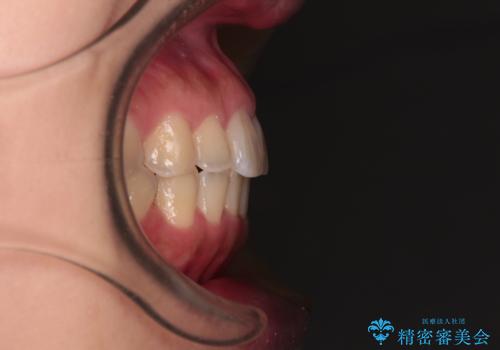

- 前歯の捻れを気にして来院された患者様です。

上顎前歯が捻れて前方に飛び出しており、下顎前歯もそれに沿うようにデコボコとなっていました。

IPR(歯と歯の間を削る処置)によりスペースを獲得して上下前歯のデコボコを改善し、インビザラインにて矯正治療を行うこととしました。

捻れていた前歯の形態が、先端が欠けていたり、一部むし歯処置により左右非対称の形態となっていたため、なかなかゴールが定まらず、治療期間がかかってしまいました。